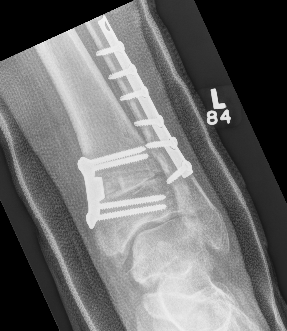

Xray

Ranges from anterior spurring to severe OA

80% of post-traumatic OA is varus

Takakura classification

| 1 | Early sclerosis and formation of osteophytes |

| 2 | Narrowing of the medial joint space |

| 3A | Obliteration of the medial joint space with subcondral bone contact |

| 3B | Obliteration of joint space over roof of talar dome, with subchondral bone contact |

| 4 | Obliteration of joint space with complete tibiotalar contact |

Type 1: Anterior spurs

Type 3A: Obliteration of medial joint space Type 3B: Obliteration medial joint space plus tibio-talar contact with varus

Type 4 complete obliteration